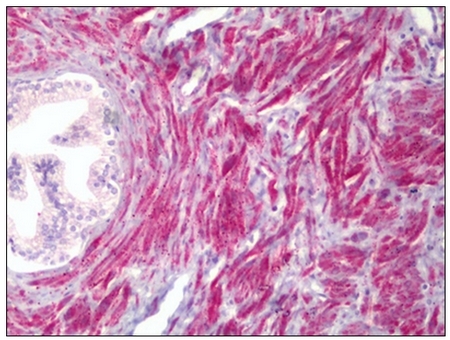

Supportive validation

- Submitted by

- OriGene (provider)

- Main image

- Experimental details

- Human Prostate, Smooth Muscle: Formalin-Fixed, Paraffin-Embedded (FFPE)

- Validation comment

- IHC